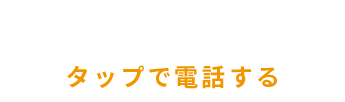

お口の中に入れた写真(一番奥の歯です)

お口の中に入れた写真(一番奥の歯です)